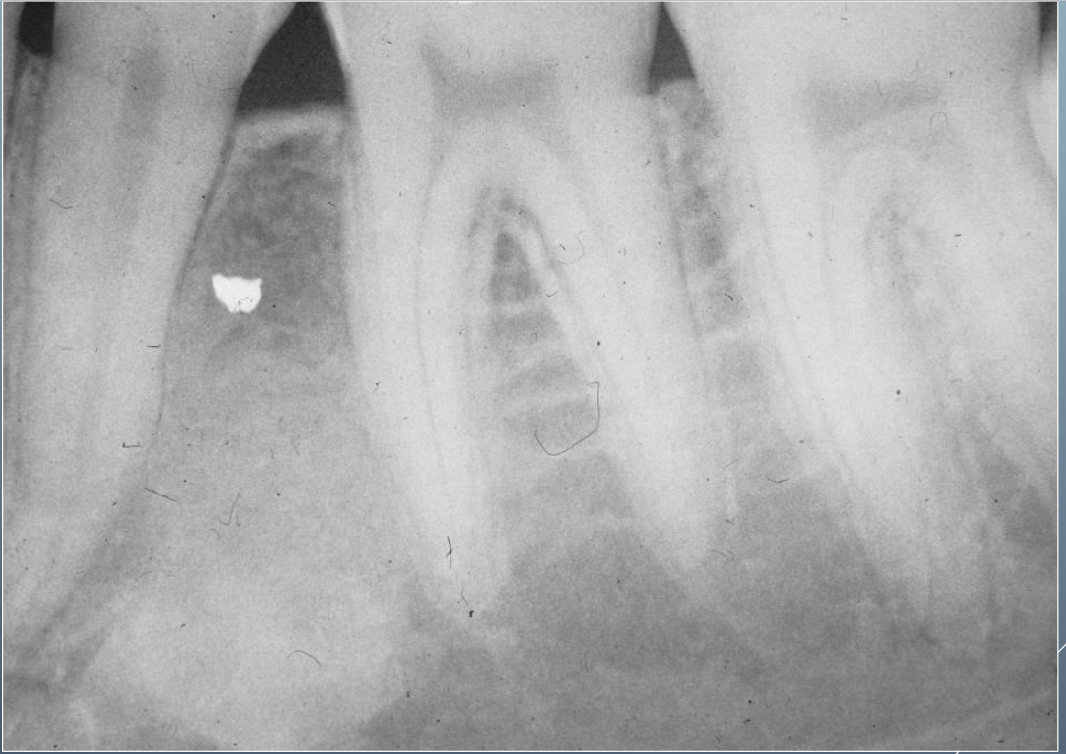

Q

What’s this?

A

HEMATOPOIETIC BONE MARROW DEFECT

FOCAL OSTEOPOROTIC BONE MARROW DEFECT

9